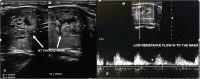

Case presentation: A 32-year-old Ugandan woman presented with a complaint of painless neck swelling of 3-months duration. The swelling was associated with a globus sensation. There was no history of thyroid - related problems or treatment prior to this presentation. Physical examination demonstrated a mobile right thyroid swelling without an obvious nodular contour. Neck ultrasound showed an absent left lobe of thyroid gland, a right lobe with a solitary nodule scoring two points on the Thyroid Imaging, Reporting and Data System (TI-RADS) and an isthmus in situ. Extensive search for possible ectopic thyroid tissue was negative. She was biochemically euthyroid. The patient was counseled about thyroid hemiagenesis and was put on a regular follow up in the clinic for the TI-RADS 2 nodule.